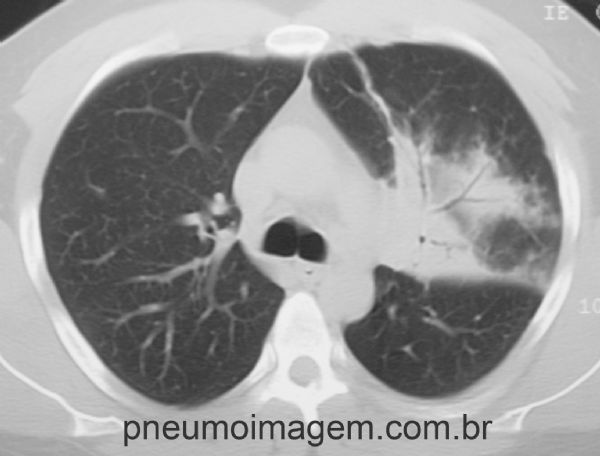

PNEUMONIA EM LOBO SUPERIOR ESQUERDO

Pneumonia comunitária demonstrada por opacidade heterogênea em lobo superior esquerdo.

Chaves: Pneumonia Adquirida na Comunidade (PAC); pneumonia lobar; pneumonia típica; condensação.

Community acquired pneumonia (CAP) demonstrated by heterogeneous opacity in the left upper lobe. Keys: typical pneumonia; lobar pneumonia; condensation.

Corte tomográfico demonstra a presença de broncogramas aéreos no interior da opacidade.

Chaves: community pneumonia; left upper lobe pneumonia.